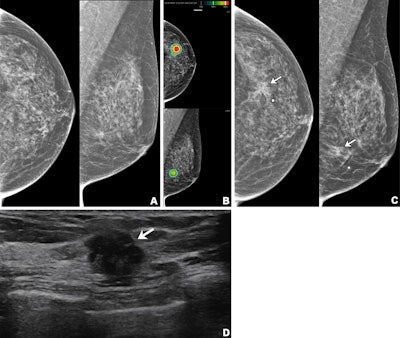

Imaging in a 56-year-old woman with heterogeneously dense breasts (BIRADS C). (A) Left craniocaudal (left) and mediolateral oblique (right) digital mammograms show no abnormality. (B) Left craniocaudal (LCC, top) and left mediolateral oblique (LMLO, bottom) mammograms with retrospectively applied AI (Lunit Insight MMG, version 1.1.7.1; Lunit) show the lesion was given abnormality scores of 97% and 71%, respectively. The color bar indicates pixel-level abnormality scores corresponding to heatmap contour lines. Breast ultrasound performed the same day was considered negative (not shown). (C) Left craniocaudal (left) and mediolateral oblique (right) digital mammograms acquired nine months later show an irregular mass (arrows) in the left breast, which correlates with the heatmap areas scored as 97% and 71% by AI in the earlier screening mammogram (B). The radiopaque round marker denotes the site of the palpable abnormality indicated by the patient. (D) Transverse ultrasound imaging shows an irregular mass (arrow) in the left breast. The patient was treated with breast-conserving surgery, and the mass was proven to be invasive lobular carcinoma. Image courtesy of the RSNA.